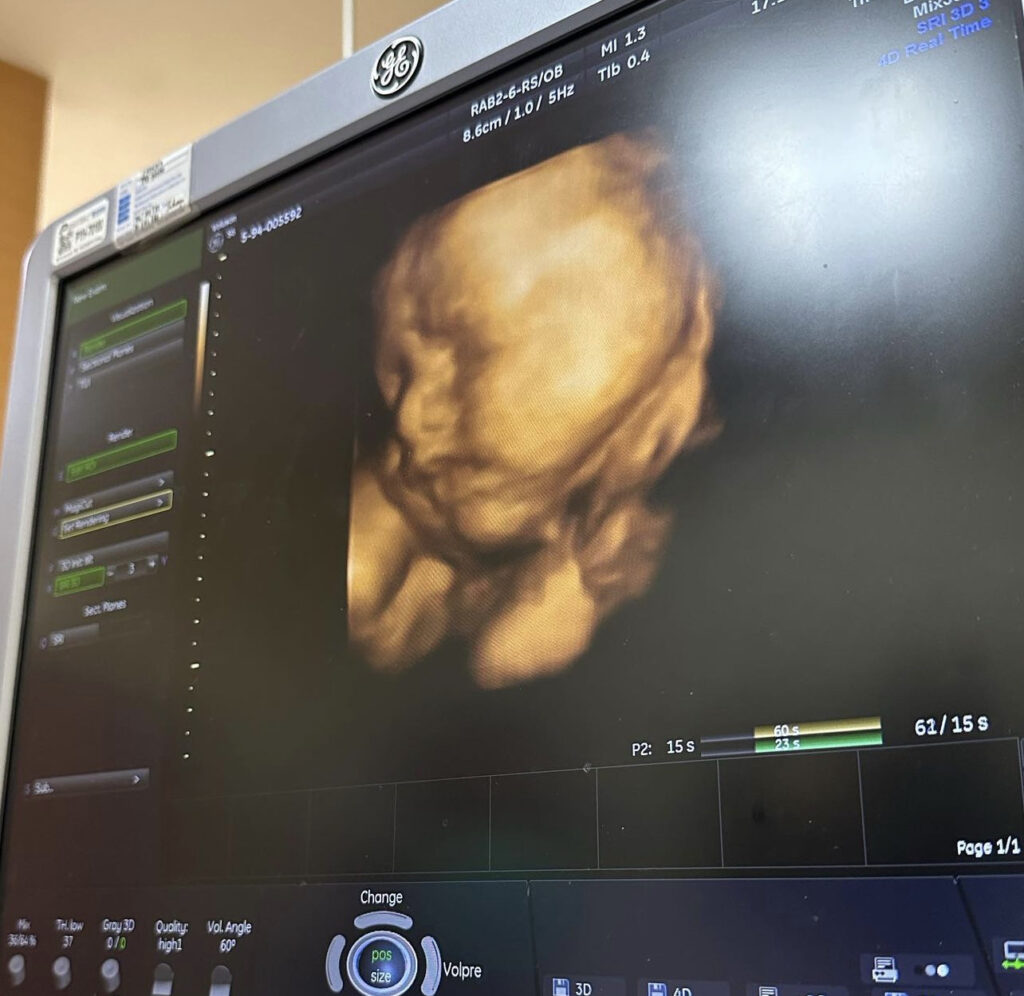

ล่าสุดสาวบุ๋ม ได้ออกมาโพสต์ภาพอัลตร้าซาวด์หน้าลูกชายครั้งแรก ให้แฟนคลับได้ยลโฉมกัน ต้องบอกเลยว่าหน้าอวบอิ่ม จมูกพุ่ง หล่อแต่ไกลมากเลยค่ะ มาพร้อมแคปชั่นว่า”หน้าเหมือนใคร??“ ซึ่งงานนี้แฟนคลับและคนในวงการบันเทิงต่างเข้ามาแสดงความยินดีกับสาวบุ๋มกันสนั่นไอจี